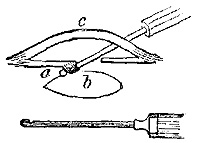

Operation.—The patient lying on his face, a straight{23} incision (Plate III. fig. 1), at least four inches in length, should be made over the artery, and thus nearer the inner than the outer hamstring; a strong fibrous aponeurosis will require division after the skin and superficial fascia are cut through, the limb is then to be flexed, and the tendons drawn aside with strong retractors; fat and lymphatic glands must next be dissected through, and then the vein and artery, lying on a sort of sheath of condensed cellular tissue, are seen, the vein lying above the artery and obscuring it. The vein must be drawn to the outside, and the thread passed round the artery, which lies close to the bone, on the ligamentum posticum of Winslowe.